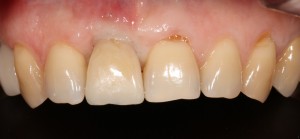

А через два месяца — вот так:

На этом этапе, для создания более правильного десневого контура, можно поменять формирователь размер больше:

А еще через месяц — поставить временную коронку:

Могли бы мы в этом случае обойтись без аугментации лунки? Вполне, могли бы. Но в этом случае окружающие коронку ткани выглядели бы иначе, а сам пациент испытывал бы проблемы с уходом — из-за утраты объемов, у него постоянно застревали бы остатки пищи между коронкой и десной.

которая через три месяца, к моменту интеграции импланта, выглядит совсем иначе:

Ну и… к моменту установки постоянной коронки, у нас сохранился естественный контур прилегающей десны.

Что, собственно, нам и требовалось сделать.